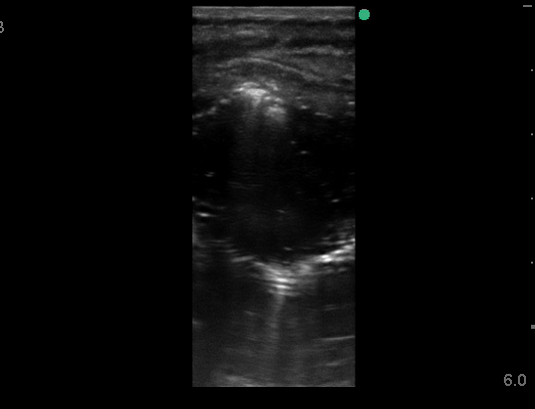

Microbubbles in Ultrasound Guided Gastrostomy